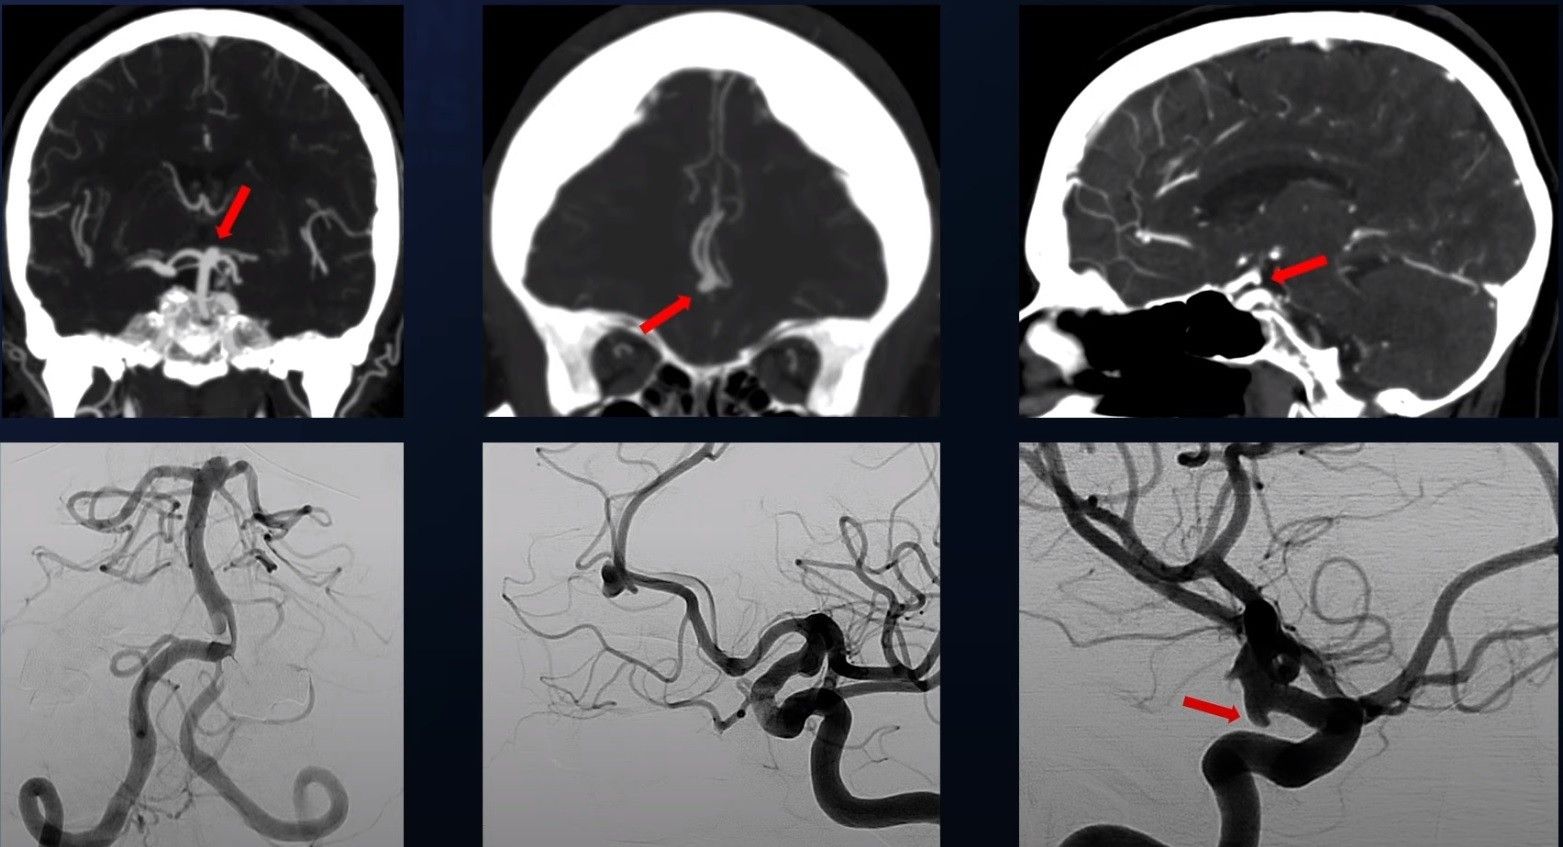

Me zhvillimin e procedurave moderne diagnostikuese, kryesisht skanerëve dhe imazherisë me rezonancë magnetike, procedurave angiografike dhe disponueshmërisë së tyre më të madhe, numri i pacientëve te të cilët aneurizma zbulohet “në kohë” para se të shpërthejë, është duke u rritur.

Pasi aneurizma zbulohet me anë të këtyre metodave, karakteristikat e saj morfologjike analizohen për të vlerësuar rrezikun e rupturës. Rreziku i rupturës së saj është më i madh me aneurizmat më të mëdha se pesë milimetra.

Aneurizmat e vendosura në bifurkacionet e enëve të mëdha të gjakut në tru, veçanërisht arteria cerebrale e mesme, arteria komunikuese anteriore dhe arteria bazilare, shoqëroheshin më shpesh me një rrezik më të lartë të këputjes. Madje, dhe aneurizmat e parupturuara mund të shkaktojnë simptoma të caktuara.

Nëse ekzistenca e një aneurizme të trurit përcaktohet si shkak i gjakrrjedhjes, fillohet trajtimi, i cili përfshin përjashtimin e aneurizmës nga qarkullimi, në mënyrë endovaskulare ose kirurgjikale. Të dyja metodat kanë avantazhet dhe specifikat e tyre dhe më shpesh vendimi për metodën e trajtimit merret në konsultim, me pjesëmarrjen e mjekëve të specialiteteve të ndryshme.

Trajtimi endovaskular i aneurizmave që nuk kanë rupturë dhe janë zbuluar “në kohë” është më i rehatshmi për pacientin. Kjo metodë përdor ekzistencën e rrjetit tonë të enëve të gjakut dhe kështu arteriet e trurit arrihen përmes arteries inguinale me një sistem të veçantë kateteri, dhe më pas aneurizma mbushet me spirale specifike platini për ta eliminuar atë nga qarkullimi. Nga ana tjetër, në rast të rupturës së aneurizmës dhe gjakrrjedhjes së madhe, trajtimi operativ ka një avantazh, sepse në këtë rast, përveç trajtimit të aneurizmës, kryhet edhe evakuimi i gjakut, i cili e çliron trurin nga prania dhe presioni i gjakut.